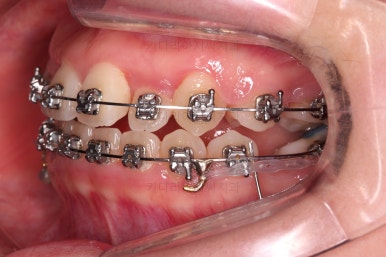

초진 때의 입안 모습입니다.

원래 다니던 치과에서 1년여 교정치료를 진행하신 상태였는데요.

몇 가지 이상한 점이 보이죠?

한 쪽만 발치가 되어있다.

아랫니에 유치가 2개가 그대로 남아있다.(화살표)

몇몇 이아에는 장치가 부착되어 있지 않다.